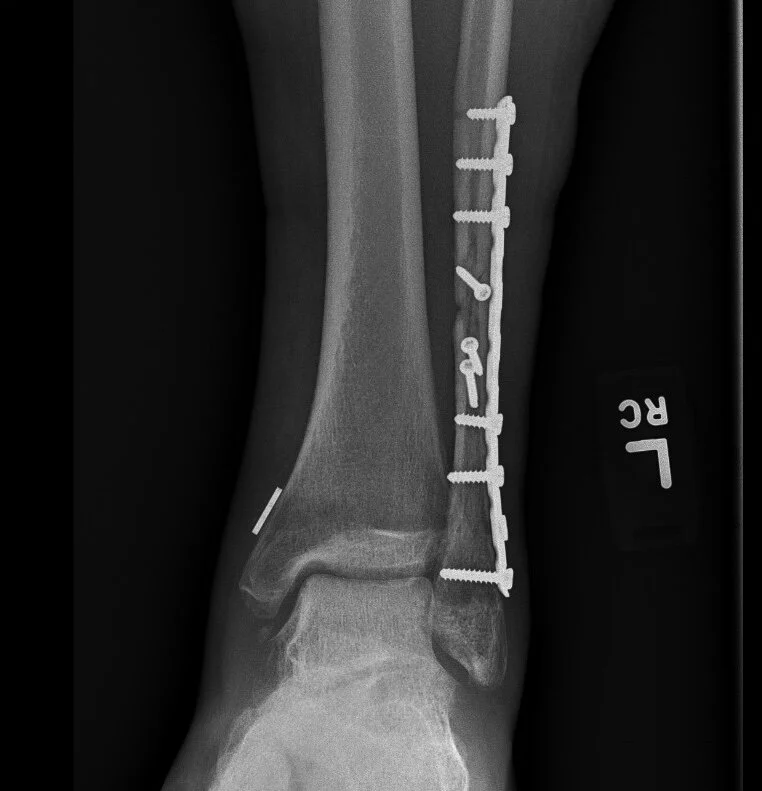

Displaced fracture of the distal third of the tibia.

Surgery for fractures involves making an incision in the skin, putting the bones back into place, and keeping the bones in place using metal devices like plates and screws. In most cases, the metal can stay inside forever without issue.

Trimalleolar ankle fracture